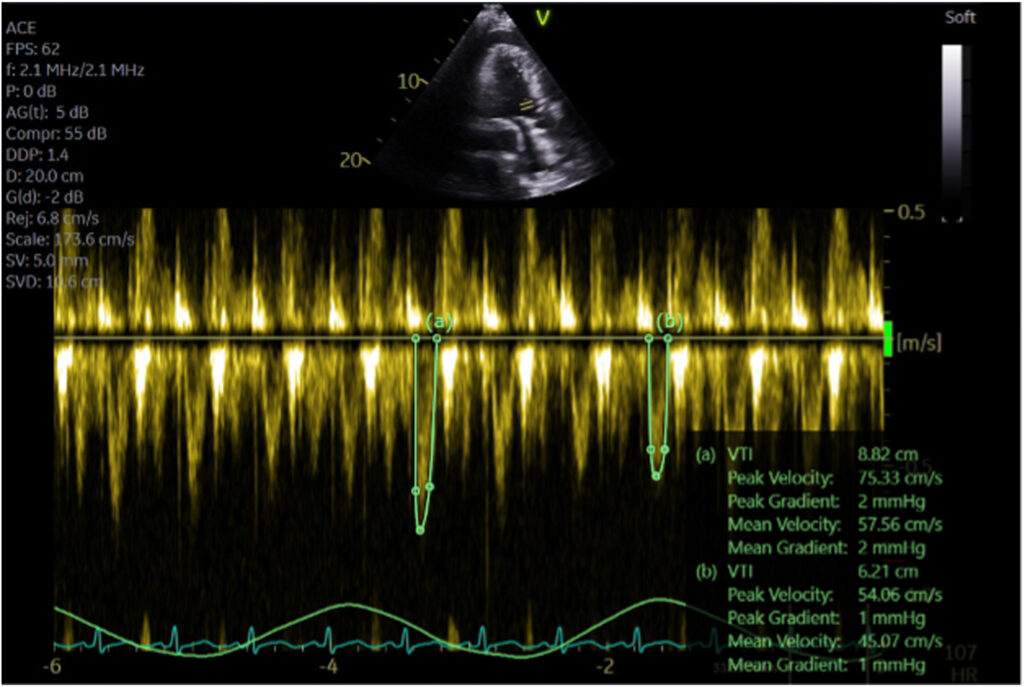

Havia ainda uma variação importante, durante o ciclo respiratório, nas velocidades dos fluxos tricúspide (aumento de 44% durante a inspiração) e mitral (redução de 25% durante a inspiração).

Durante a inspiração, a velocidade de pico do fluxo na via de saída do VE reduzia 28% (0.75 –> 0.54 m/s).

A VTI, avaliada na janela apical 3C, foi de 8.8 cm para 6.2 cm, conferindo uma redução de 30% durante a inspiração. Tal achado é consistente com a variação inspiratória do volume sistólico ejetado. A veia cava inferior estava pletórica (2.3 cm) com variabilidade inspiratória de 22%. Ainda, havia fluxo reverso na veia hepática durante a expiração.